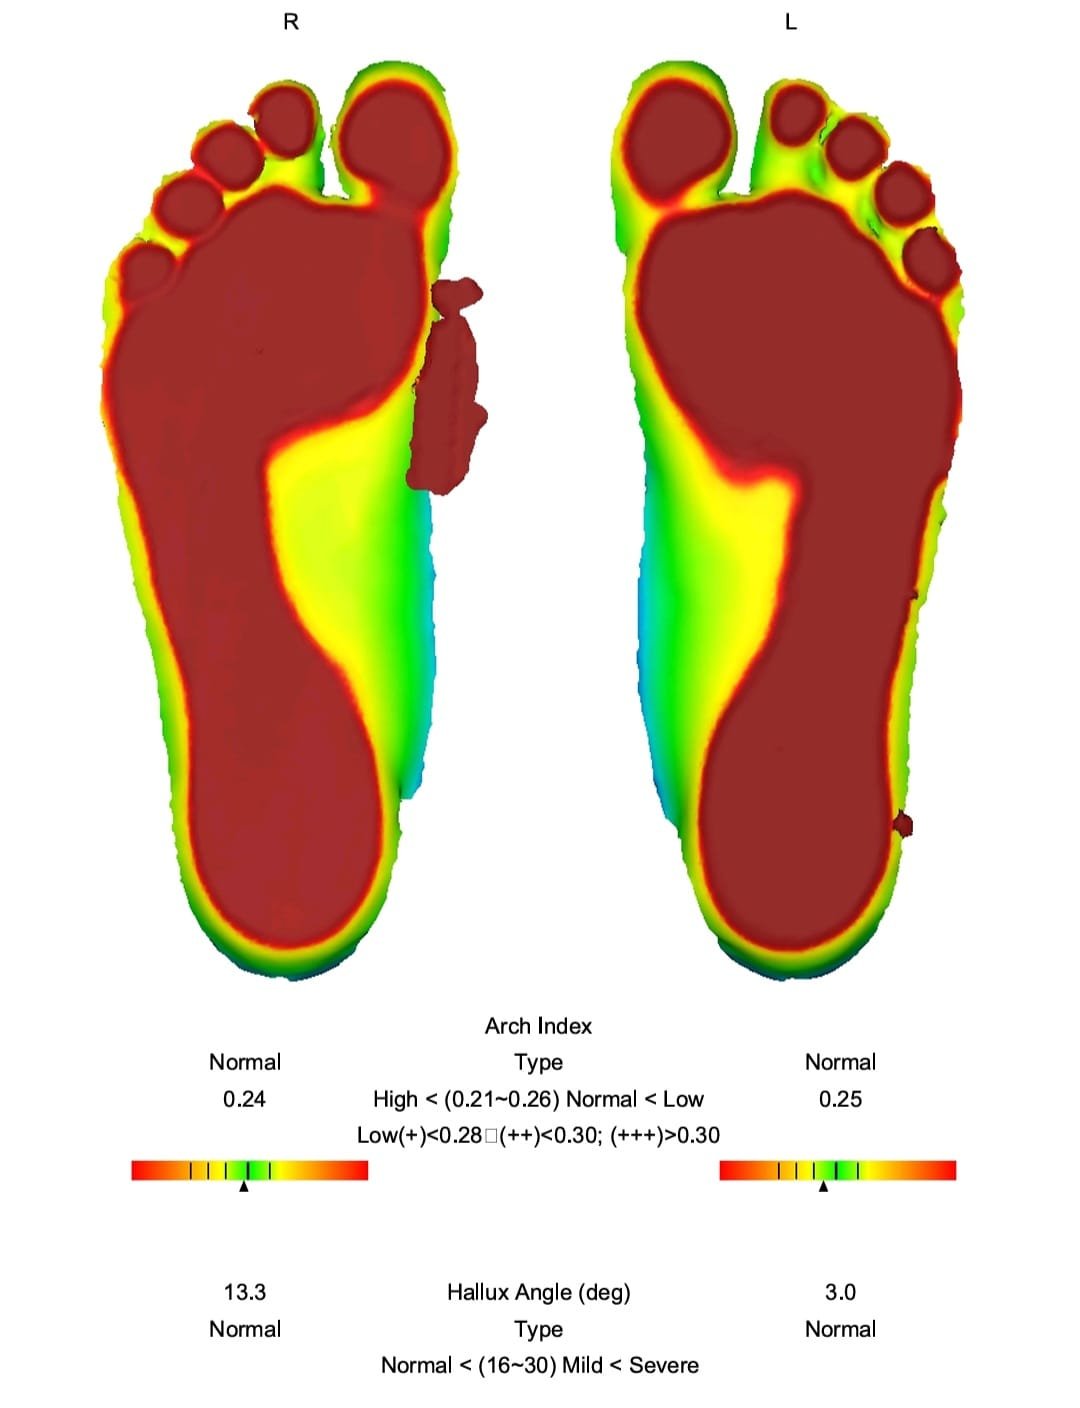

Con nuestro footscan 3D, analizamos tu huella plantar, detectando alteraciones como pie plano, cavo o mixto.